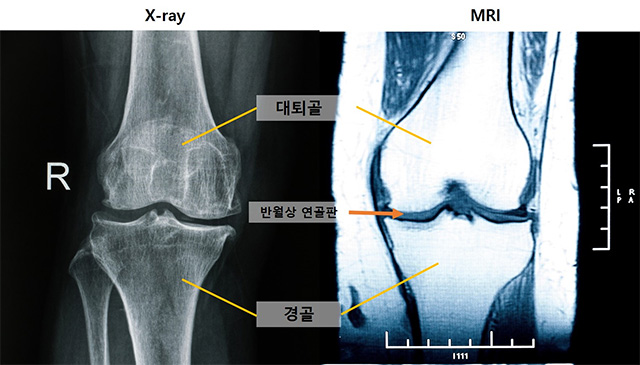

• (왼쪽부터)엑스레이 및 MRI 무릎 사진 /출처=게티이미지뱅크(서울대병원 제공)

▲ (왼쪽부터)엑스레이 및 MRI 무릎 사진 /출처=게티이미지뱅크(서울대병원 제공)

분석 결과, 관절염 진행에서 가장 먼저 나타나는 변화는 ‘중앙 대퇴골 연골 손상’이었다. 이는 엑스레이상 정상으로 분류되는 관절염 0기(KL 0기)에서도 관찰돼, MRI가 조기 변화를 포착하는 중요한 도구임을 보여줬다.

연구팀은 ‘반월상 연골 탈출(extrusion)’이 무릎 관절염 진행 위험을 강하게 예측하는 지표라는 사실도 확인했다. 이는 단순한 추적 기간보다 무릎 내부의 구조적 변화가 질환 악화에 더 큰 영향을 미친다는 의미다.

MRI에서 먼저 발견된 변화는 시간이 지나면서 엑스레이에서도 확인됐다. 구체적으로는 경골 골극, 내측 관절강 협착, 대퇴골 골극 순으로 나타났으며, 모두 MRI에서 확인된 연골 손상과 밀접하게 연관돼 있었다.